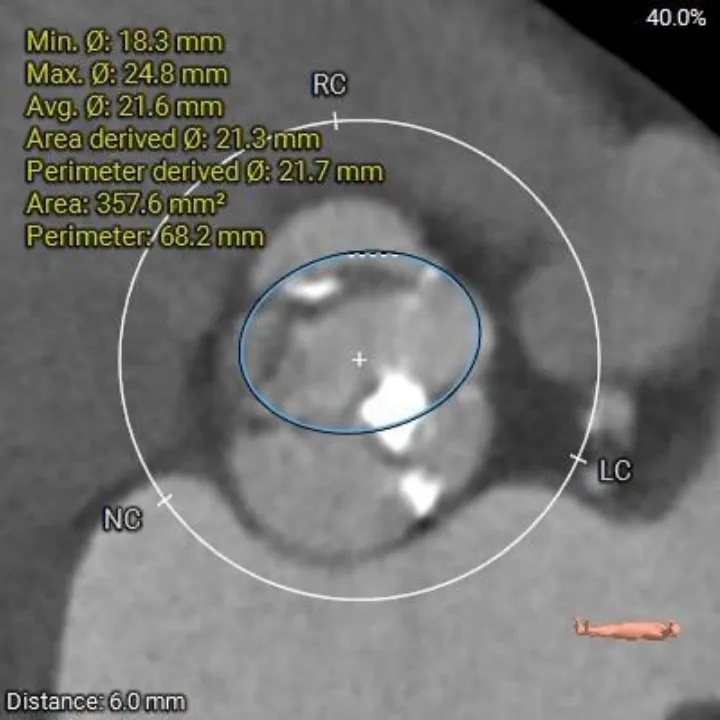

瓣上结构测量

瓣上2mm

21.6mm

瓣上4mm

21.9 mm

瓣上6mm

21.7 mm

瓣上8mm

21.7mm

瓣上10mm

21.1mm

瓣上限制较重,可见明显左窦瓣叶偏心钙化,限制最重区域为瓣上4-8mm。